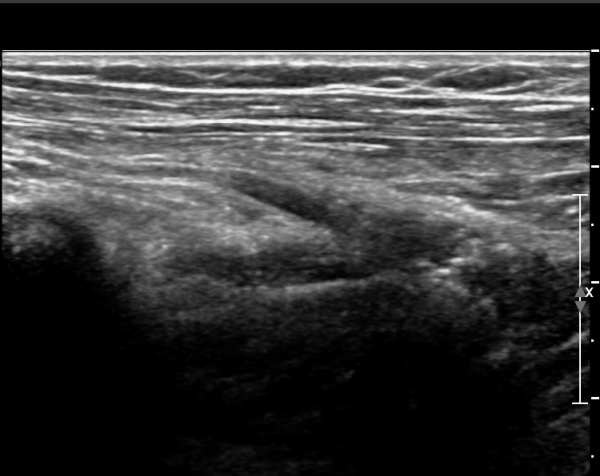

¼ÒµÎ(capitulum) À§Ä¡¿¡¼­ Èİñ°£½Å°æ Ⱦ´Ü¸é°Ë»ç»ó Èİñ°£½Å°æÀÌ Àú¿¡ÄÚ ÀÛÀº ¿øÇüÀ¸·Î

°üÂûµÈ´Ù(»çÁø 1)